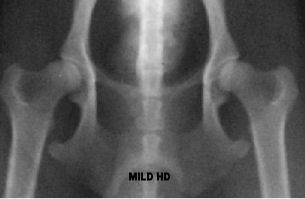

Below are hip x-rays of Cavaliers showing most of the grades of

classification. I don’t have a copy of a Borderline or a Severe.

You can find examples from other breeds online if you are

interested. You can easily see in each x-ray how there is less

and less coverage of the head of the femur (the femoral head—the

round ‘ball’ at the ‘top’ of the leg bone) and the acetabulum

(the ‘cup’ where the femoral head sits) gets more shallow as the

status of the hips declines until they barely overlap at all. In

a severe there is basically no overlapping whatsoever.